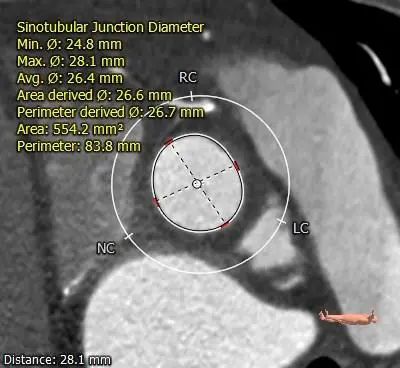

STJ

瓦氏窦内径可,窦管交界、升主动脉内径可。